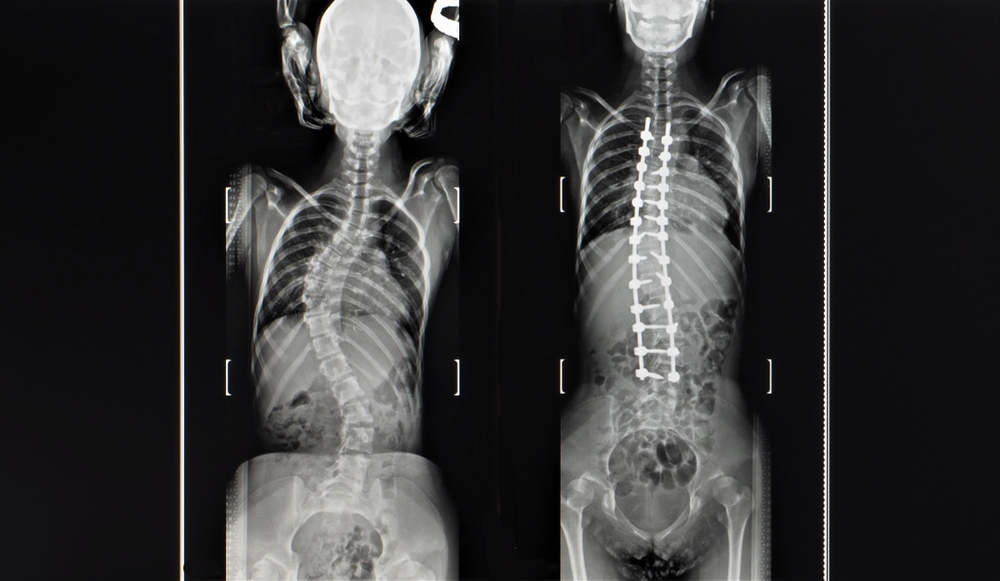

28/02/2024 14:53Sim, a escoliose pode causar dor em alguns casos. Isso ocorre porque a curvatura anormal da coluna vertebral pode levar à tensão muscular e, em alguns casos, pode causar danos aos discos da coluna vertebral, nervos ou até mesmo aos pulmões e coração. Portanto, se o seu filho foi diagnosticado com escoliose e está com dores, é importante consultar o médico para discutir as opções de tratamento. A fisioterapia, por exemplo, pode ajudar a aliviar a dor e a fortalecer os músculos ao redor da coluna. Em casos mais severos, pode ser necessária a intervenção cirúrgica. Lembre-se sempre de buscar o auxílio de um profissional de saúde para o correto diagnóstico e tratamento.